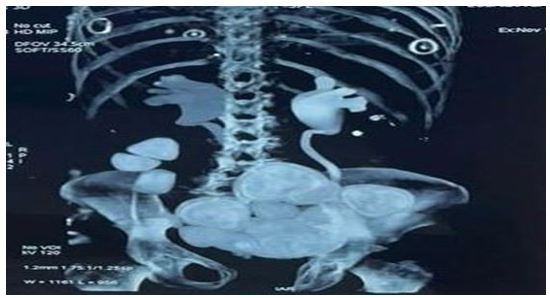

Continent urinary diversion, such as Benchekroun hydraulic valve, are a useful adjunct in the elaboration of continent urinary reservoir. This valve can be installed either as a salvage technique for failed efferent lambs or as a de novo application on conventional ileocolic bladders [1]. We report the case of a 46-year-old female patient who underwent 18 years ago a cystectomy for bladder exstrophy and a neobladder reconstruction with a Benchekroun hydraulic valve. Later on, the patient has developed a schizophrenia and stopped doing the self-catheterization. She was taken to the emergency department by her family for a deterioration of general condition. The blood sample found a renal failure with a hyperkalemia at 7mEq/L and a CT-Scan showed a bilateral pyelocaliceal dilation with multiple big neobladder stones. The patient unfortunately passed away due to a respiratory distress secondary to her nephrogenic pulmonary edema. We therefore highlight the role of self-catheterization in continent urinary diversion otherwise severe complications can occur such as bladder stones or renal failure. Another point to emphasize is the absence of cognitive disorders so the patient can ensure an intermittent self-catheterization.

Figure 1: CT-Scan Showing Multiple Bladder Stones

Figure 2: CT-Scan Showing Bilateral Pyelocaliceal Dilation